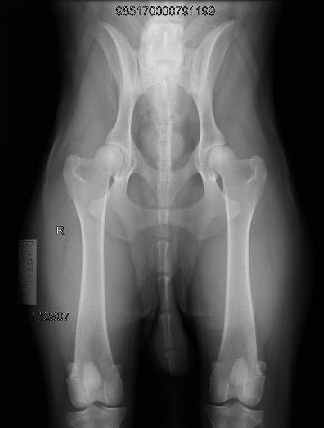

צילומי אגן לוועדת היפ דיספלסיה

בכלבים גזעיים בעלי תעודות יוחסין מבצעים צילומי אגן בהרדמה בדרך כלל מעל גיל שנה. לכל גזע קיים תקנון גידול משלים בו כתוב באיזה גיל ניתן לבצע את הצילום. צילום האגן נשלח לוועדת ההיפ דיספלסיה של ההתאחדות הישראלית לכלבנות המונה שלושה רופאים וטרינרים מומחים ברדיולוגיה.

הכלב מקבל ציון על רמת הפגיעה באגן שלו, הציונים נעים בין A ל E. ציון אגן A לכלב בריא ועל פי חומרת הפגיעה באגן B,C,Dבהתאמה עד לציון E לכלב חולה. בעזרת צילומי האגן נעזרים המגדלים ומבצעים הרבעות מבוקרות על מנת לשפר את הסיכויים לקבל גור בריא שלא יסבול בעתיד מבעיות אגן. צילום האגן נעשה בהרדמה מלאה והוא פעם בחיים ולכן חשוב לבצע את הצילום בצורה הנכונה והמדויקת ביותר.

ד”ר ג’רסי לזר, בשל היותו וטרינר ומגדל של כלבי הקאנה קורסו מבית הגידול Gerassi Corso, פיתח מתקן שעוזר להגיע לשלמות בביצוע הצילום. השלמות במנח הכלב והמהירות בה מגיע ד”ר ג’רסי לזר לצילום המושלם, בעזרת המתקן שלו, למעשה מקצר את משך זמן ההרדמה ובכך בטוח יותר לכלבכם. ד”ר ג’רסי לזר צבר ניסיון רב בתחום צילומי האגן בכלבנות הגזעית ומבצע צילומי אגן לכל גזעי הכלבים משנת 2000. לד”ר ג’רסי לזר רנטגן דיגיטאלי מודרני וחדשני, ובנוסף מעניק יעוץ ועזרה חינם בכל ההליך מול וועדת ההיפ דיספלסיה של ההתאחדות הישראלית לכלבנות.